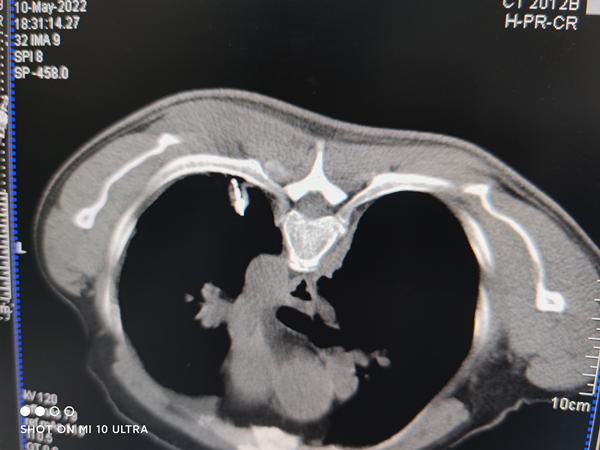

去年9月,张先生因肝硬化,伴食管胃底静脉曲张破裂出血,到当地医院就诊,却没想到,肝硬化和静脉曲张破裂还没治好,先查出来了另一个疾病——根据胸部CT显示,患者的左肺下叶背段占位性病变,考虑周围型肺癌

因为当时主要是为了治疗肝硬化伴食管胃底静脉曲张破裂出血的病症,所以,张先生当时并没有病理活检。直到今年4月份,张先生发现近来自己偶尔咳嗽出现了咳血的症状,想到了去年疑似肺癌的CT报告,这才来到了广东药科大学附属第三医院肿瘤科一区检查。

经过病理活检,张先生确诊肺浸润性腺癌